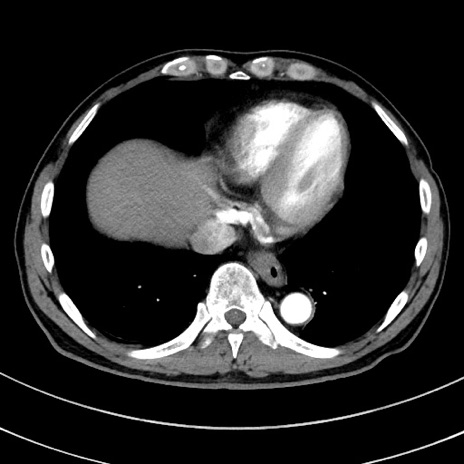

症例8(横断像)

【症例】 60歳代男性

【主訴】 黒色吐物

【現病歴】 4日前から嘔気自覚、2日前の朝食後にも嘔気あり、自分で手で嘔吐反射起こし嘔吐したところ血が混ざっていたため受診。

【既往歴】 5年前汎発性腹膜炎を伴う急性虫垂炎で手術、高血圧、前立腺肥大症、高脂血症

【身体所見】 腹部正中に手術癩痕あり 腹部平坦・軟圧痛なし膨満感あり

【データ】WBC 8400、CRP 4.54